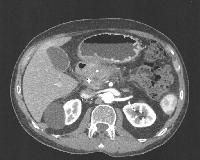

Πρόκειται για άνδρα ασθενή 67 ετών, ο οποίος, ύστερα από επεισόδιο οξείας χολολιθιασικής παγκρεατίτιδας, ανέπτυξε περιχαρακωμένες άσηπτες παγκρεατικές νεκρώσεις (WON, sterile), κυρίως στην κεφαλή του οργάνου (εικόνα 1). Κατά την επούλωση της νεκρωτικής βλάβης αναπτύχθηκε καλοήθης στένωση της ενδοπαγκρεατικής μοίρας του χοληδόχου πόρου, γεγονός που οδήγησε σε επεισόδια χολαγγειίτιδας. Η ενδοσκοπική διαστολή της στένωσης και η τοποθέτηση ενδοαυλικού stent με τη χρήση ERCP (δύο φορές) δεν ήταν λυσιτελής. Ο ασθενής οδηγήθηκε στο χειρουργείο όπου, αφού αφαιρέθηκε το stent που είχε τοποθετηθεί με την ERCP (εικόνα 2), υποβλήθηκε σε πλαγιο-τελική χοληδοχο-νηστιδική αναστόμωση (εικόνα 3) με τη χρήση οπισθοκολικής έλικας μήκους 70 cm κατά Roux en Y (εικόνα 4). Έκτοτε, ο ασθενής είναι ελεύθερος επεισοδίων χολαγγειίτιδας.